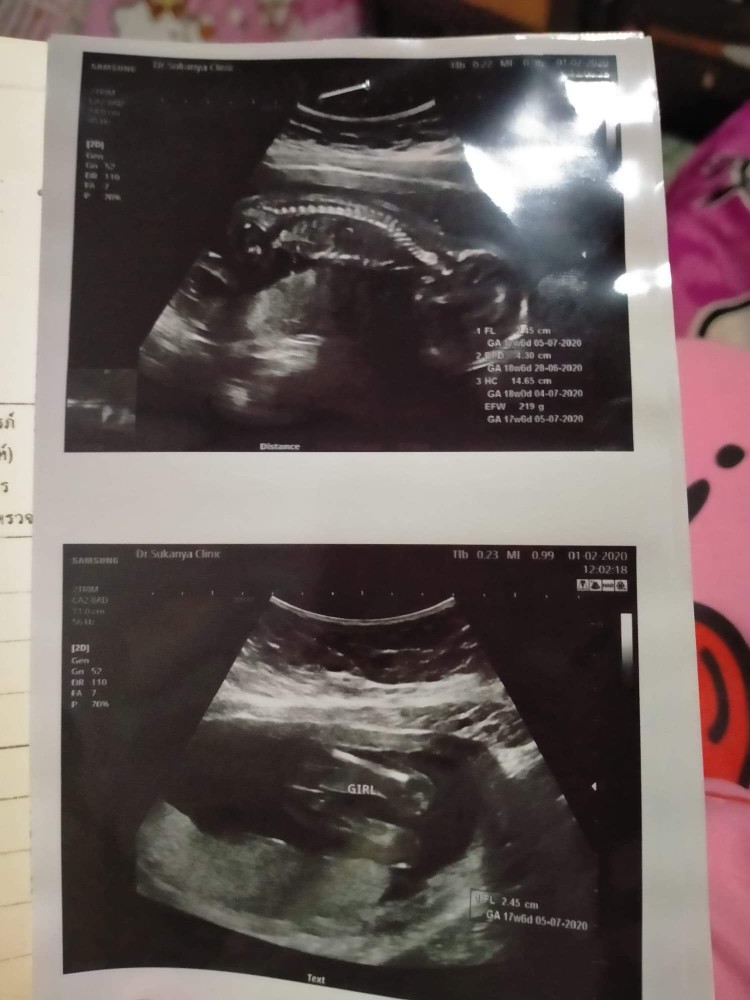

5 ก.ค ผู้กญิงจร้าา

4 ก.ค ผู้หญิงค่ะ😄